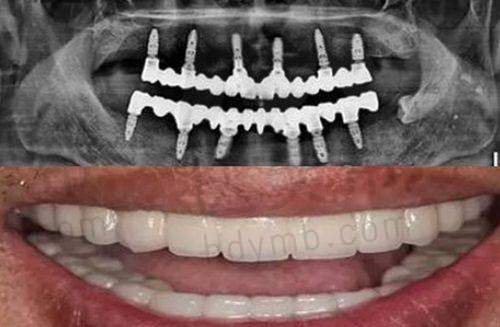

牙齿种植 | 使用方便,坚固稳定,不易松动,使用时间长,和真牙功能色泽接近 | 5000 - 260000元 |

在牙齿矫正手术方面,成效显著。医生手法熟练,在复查时会根据患者的修复情况进行调整,更终的修复成效佳。例如,有患者表示自己在该门诊部进行牙齿矫正后,不仅牙齿变得整齐美观,而且咬合功能也得到了改善。